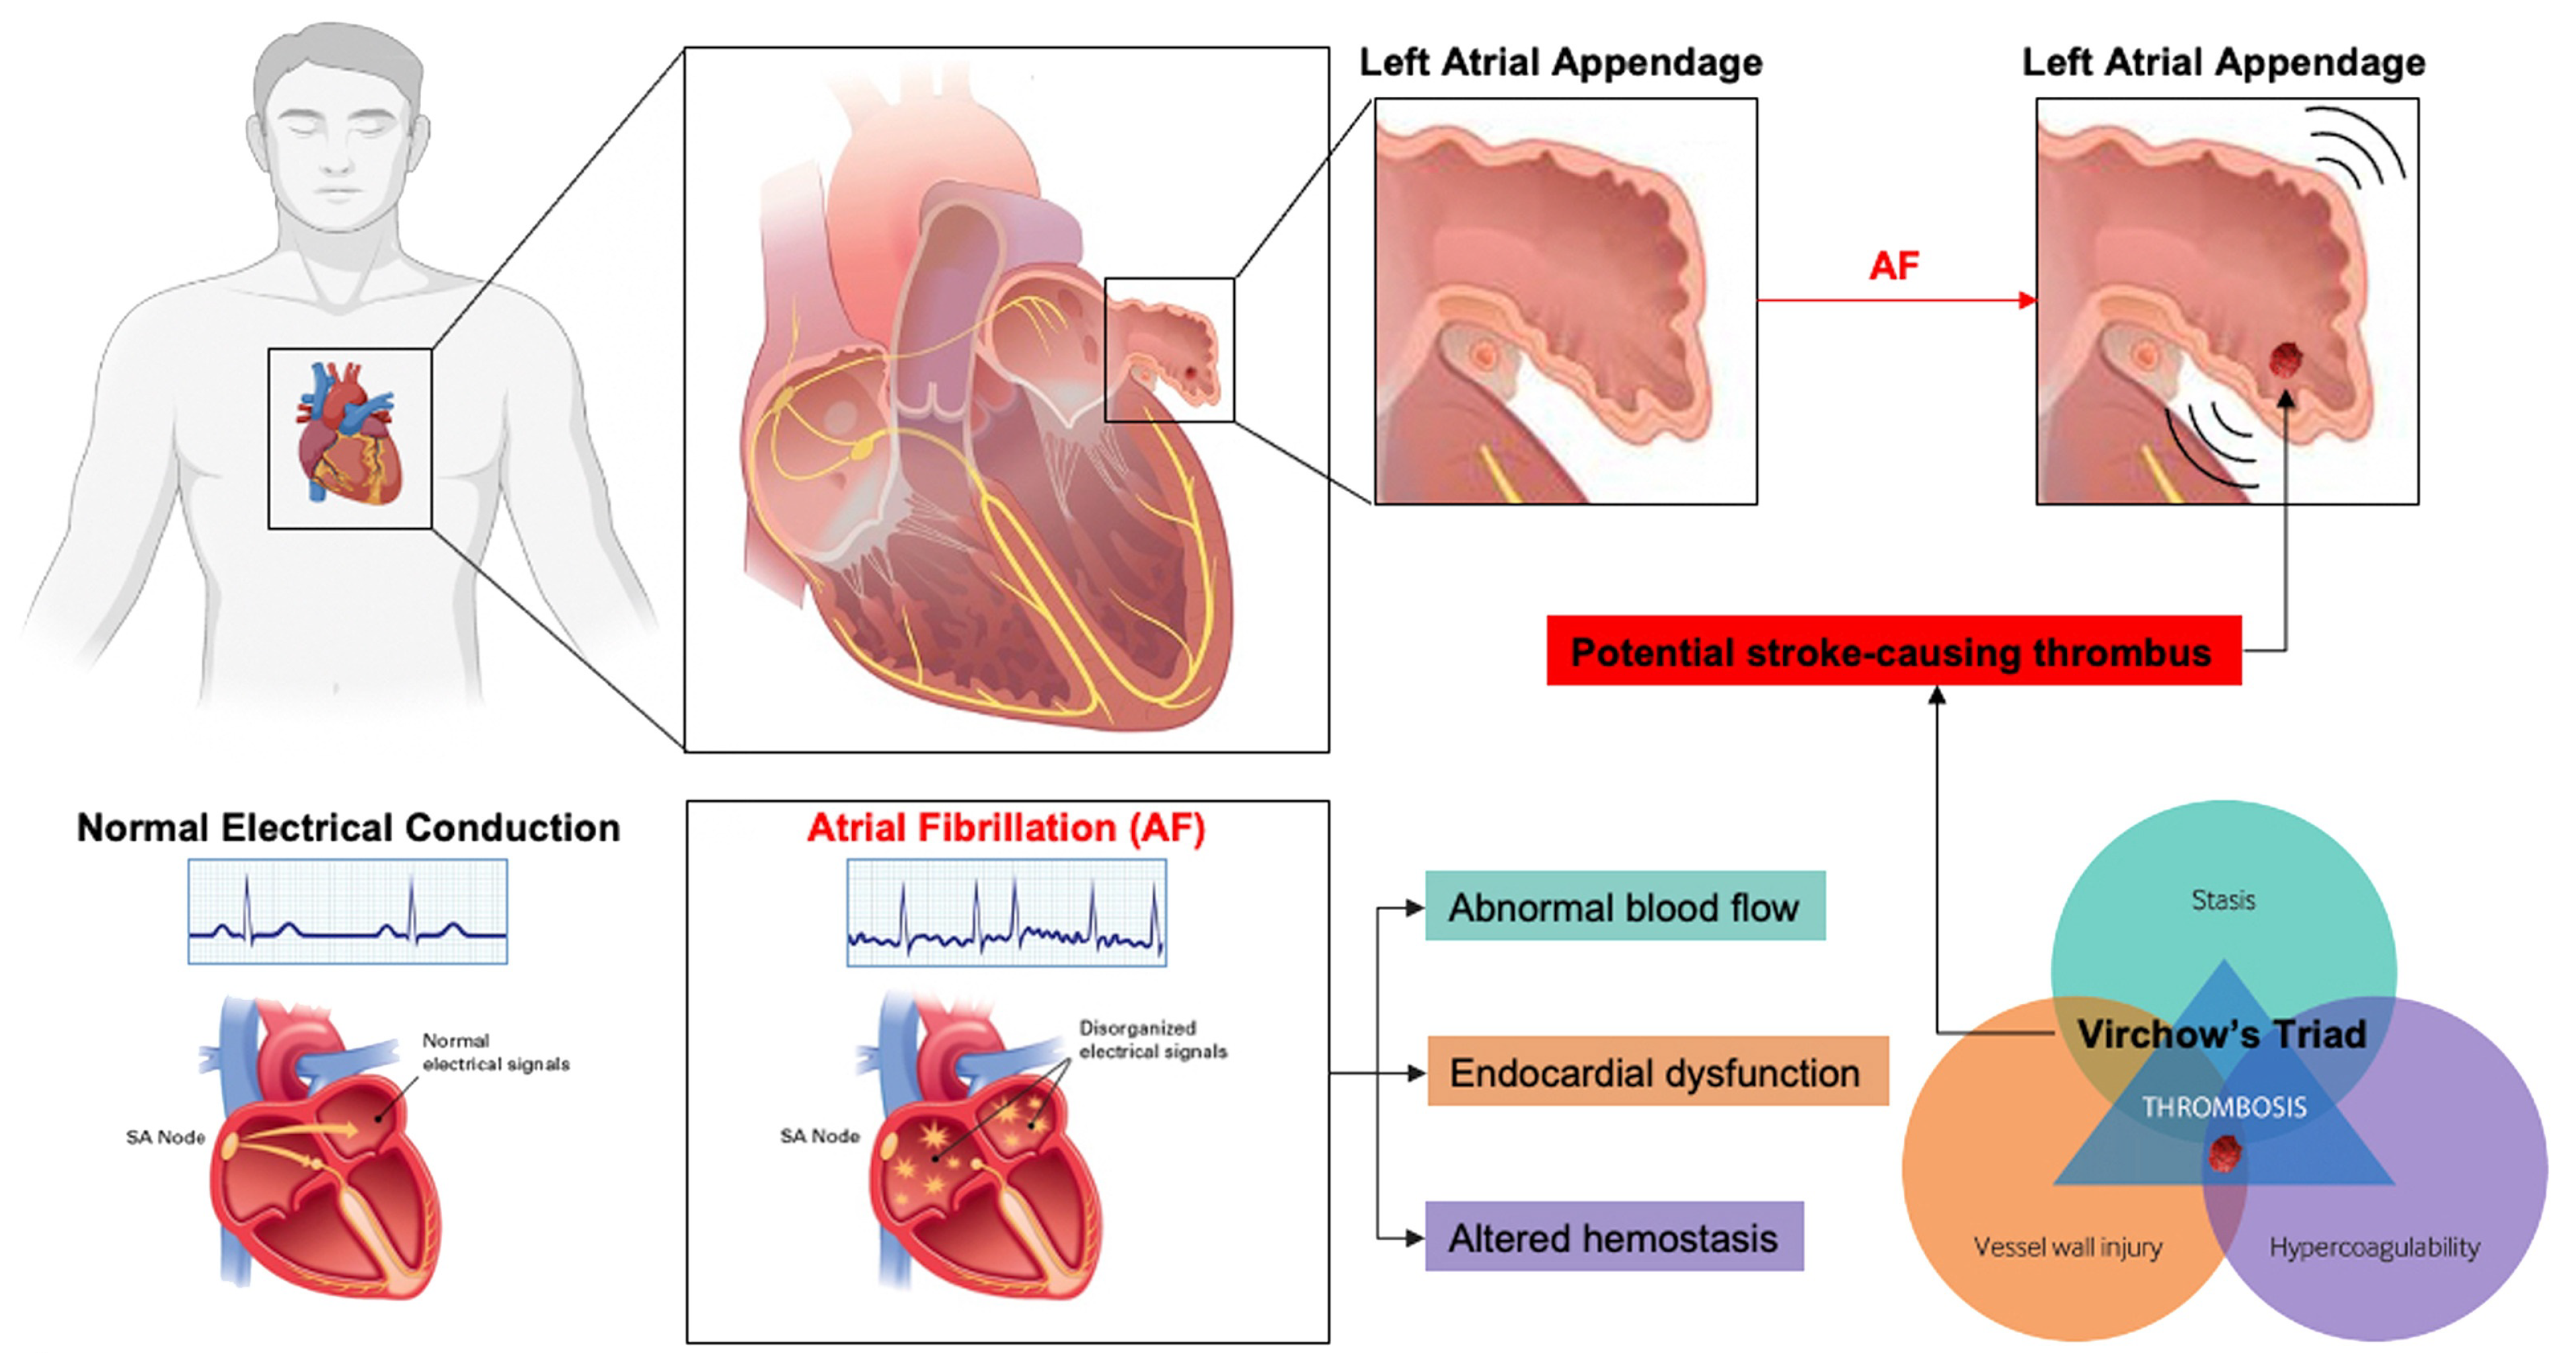

1.1. Left Atrial Appendage and Stroke Prevention in Patients Experiencing Atrial Fibrillation

1.2. Definition and Implications of Persistent PDL